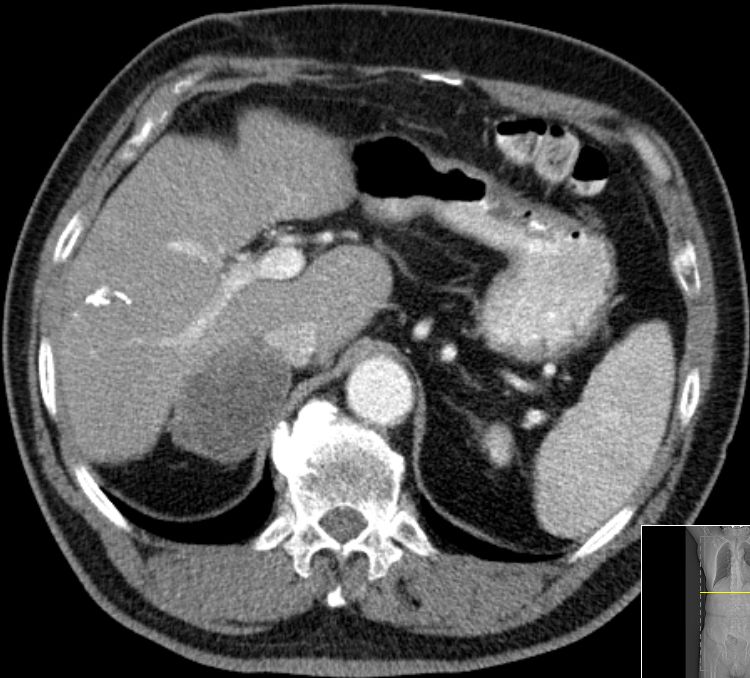

| Beispiele bildgebender Diagnostik von primären Colonkarzinomen | Zökum |

| Beispiele bildgebender Diagnostik von lokalen Metastasen | Lymphknotenmetastasen![]() |